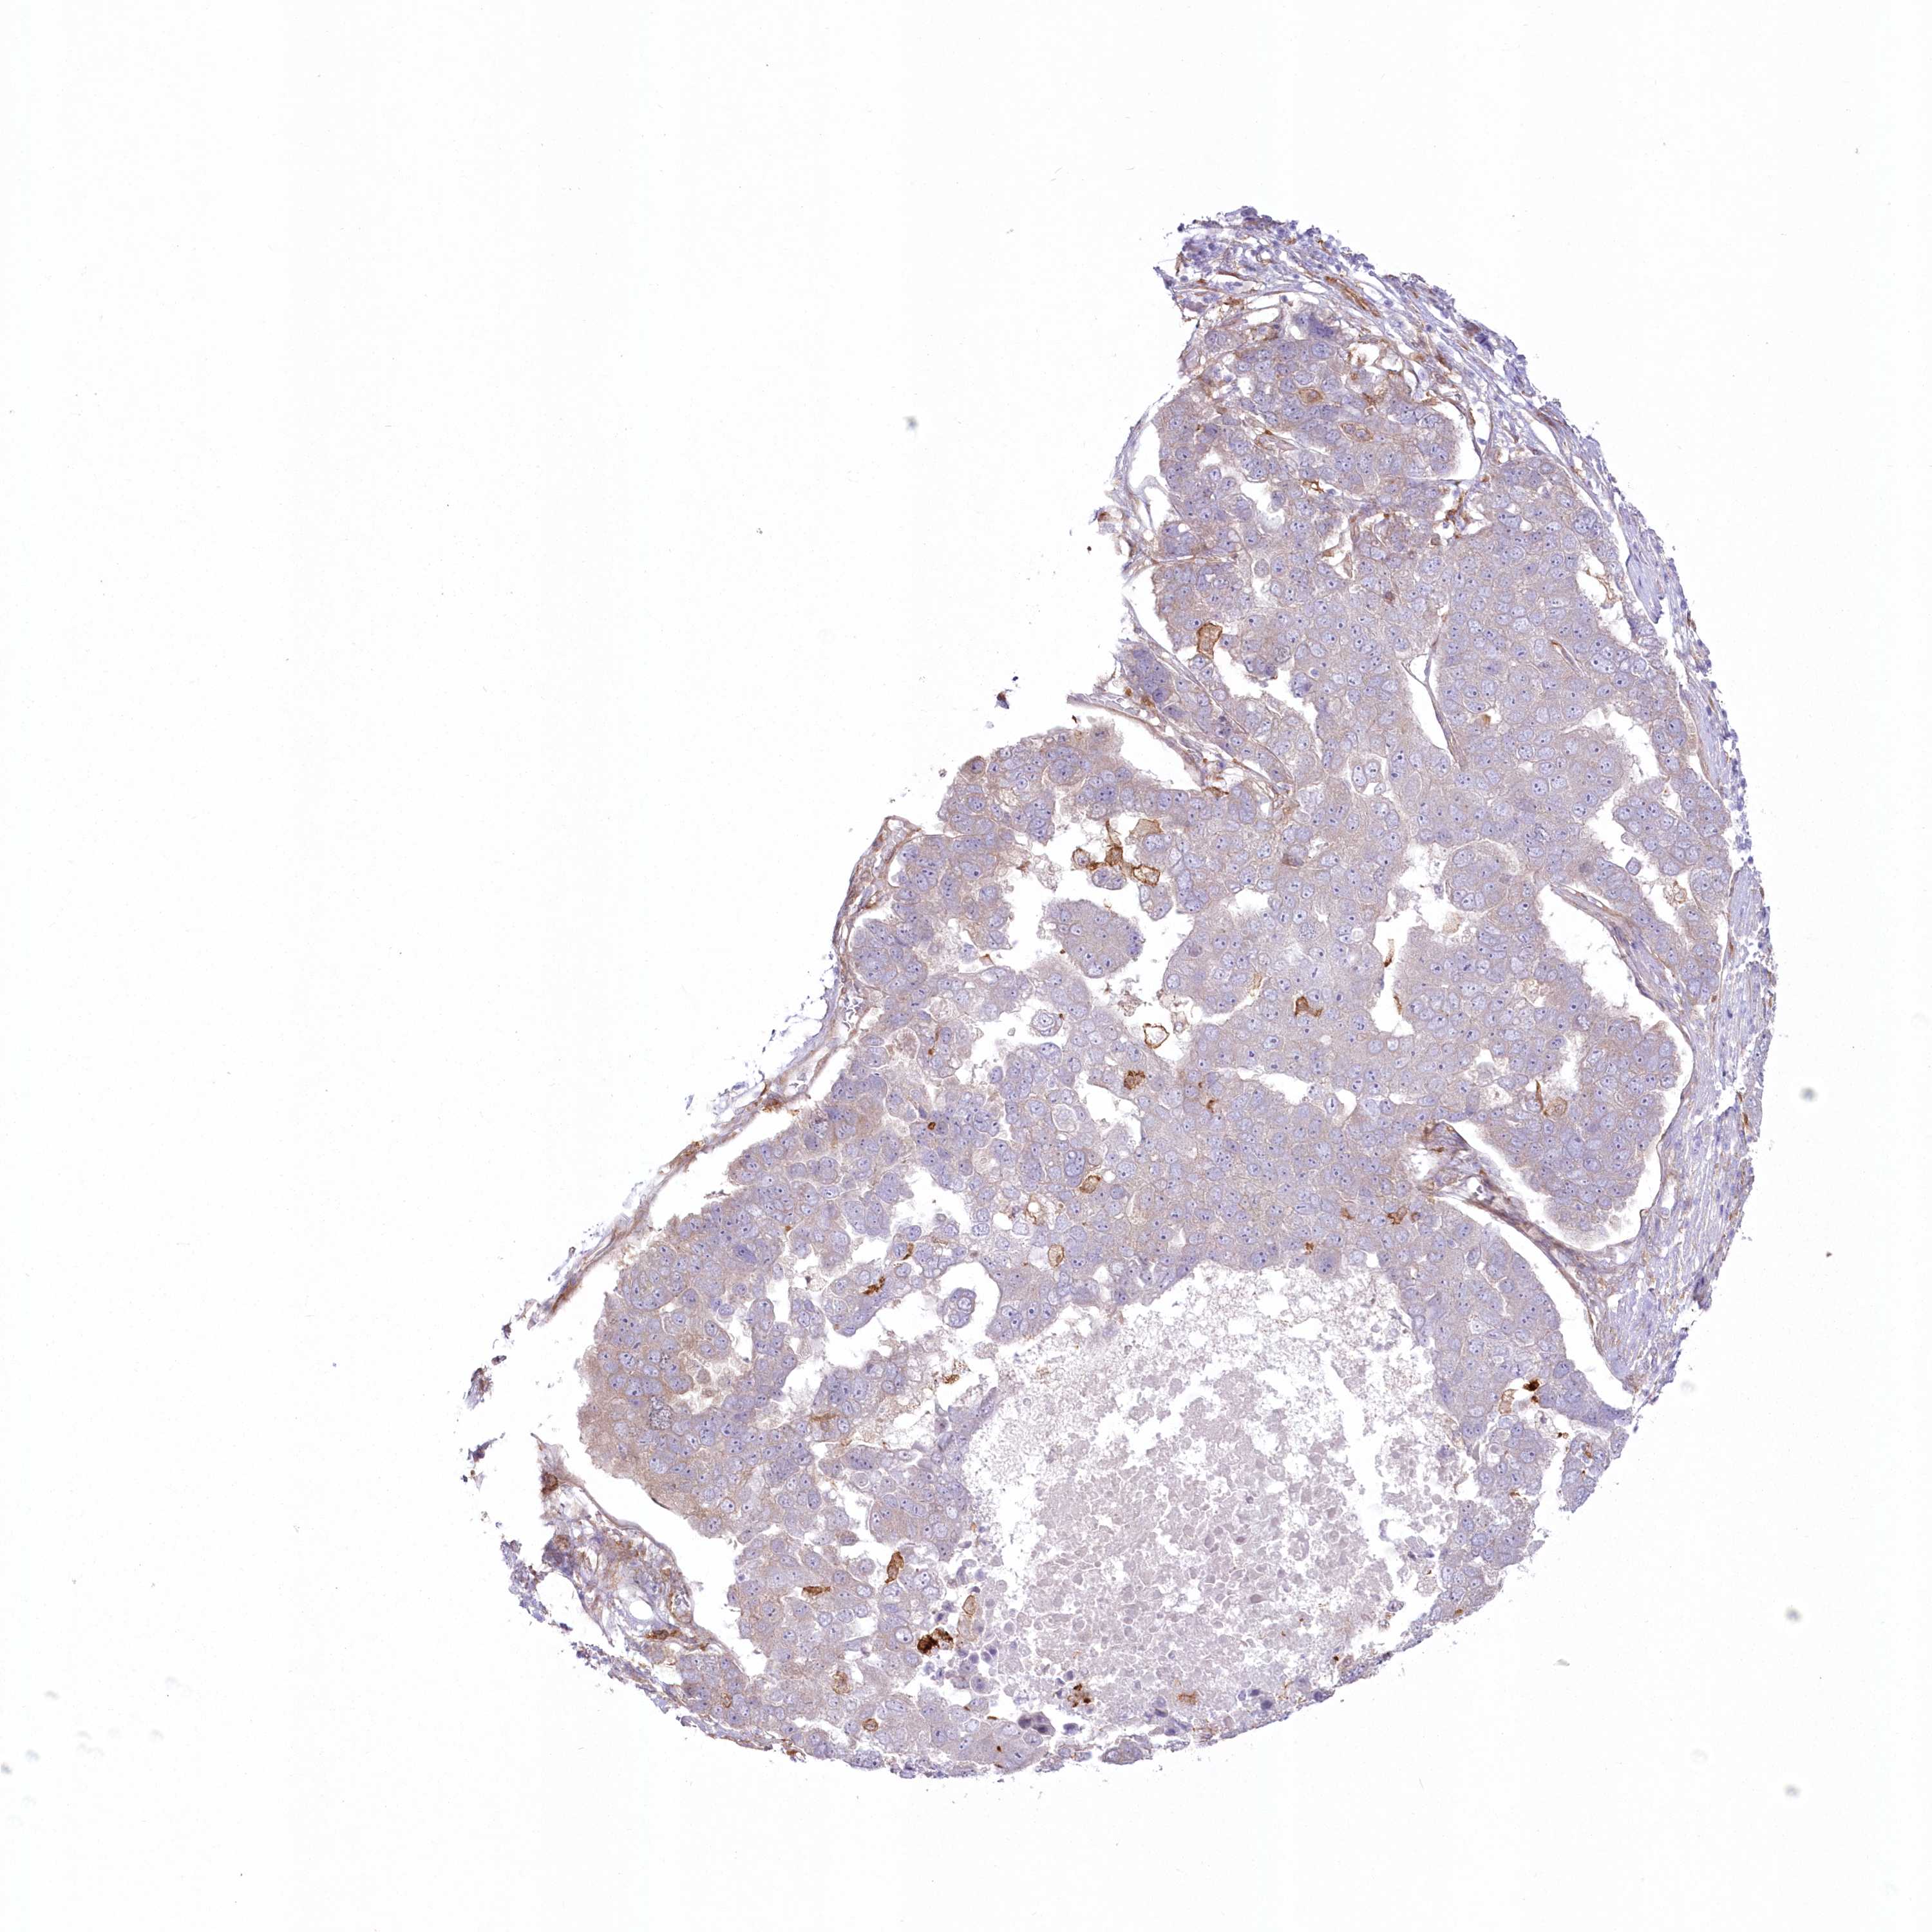

PANCREATIC CANCER - Protein expressioni

A mouse-over function shows sample information and annotation data. Click on an image to view it in a full screen mode. Samples can be filtered based on level of antibody staining by selecting one or several of the following categories: high, medium, low and not detected. The assay and annotation is described here.

Note that samples used for immunohistochemistry by the Human Protein Atlas do not correspond to samples in the TCGA dataset.

Antibody stainingi

Antibody staining in the annotated cell types in the current human tissue is reported as not detected, low, medium, or high, based on conventional immunohistochemistry profiling in selected tissues. This score is based on the combination of the staining intensity and fraction of stained cells.

Each image is clickable and will lead to virtual microscopy that enables deeper exploration of all samples and also displays staining intensity scores, fraction scores and subcellular localization as well as patient and tissue information for each sample.

Antibody HPA036471

Staining

High

Medium

Low

Not detected

Intensity

Strong

Moderate

Weak

Negative

Quantity

>75%

75%-25%

<25%

None

Location

Nuclear

Cytoplasmic/membranous

Cytoplasmic/membranous,nuclear

Adenocarcinoma, NOS